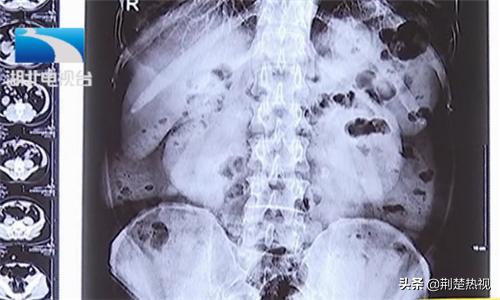

武汉京都结石医院泌尿结石医生张辉解释:“双肾都有积水,主要是右边积水比较重,大概是4公分左右,左边的积水是2公分左右,结石的大小大概都是在2公分左右。”积水严重,且左右两侧输尿管被结石和息肉包裹。如不及时处理结石梗阻问题,随时有危及生命的风险。